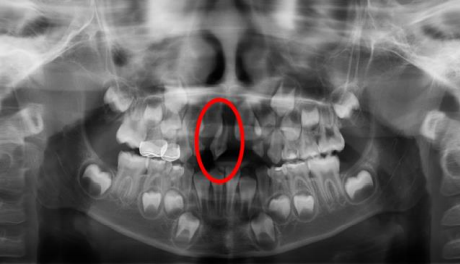

En la vasta mayoría de los casos, los dientes supernumerarios están impactados y sólo pueden ser visibles radiográficamente (12). La posición de los mesiodens normalmente es evaluada con estudios radiográficos, en la que se incluyen las radiografías periapicales, las oclusales y las ortopantomografías (figura 2), ya que facilitan el proceso de diagnóstico de mesiodens. Aunque las radiografías panorámicas son la mejor herramienta para el diagnóstico de los dientes supernumerarios, también pueden ser engañosas en algunos casos, ya que la claridad en la región de la línea media es limitada para el diagnóstico de los mesiodens. Para una visión más precisa en la región de los incisivos, también es útil la radiografía periapical anterior, y para mejorar la localización y cuando exista incertidumbre en el diagnóstico, la radiografía de tipo oclusal provee información útil en esta alteración. Con la técnica de paralelismo, se puede evaluar la posición bucolingual de los mesiodens no erupcionados (6,13,23,28). Hoy en día, el estudio de elección para el diagnóstico de los mesiodens es la tomografía conebeam (CBCT). El Conebeam provee información invaluable como la localización exacta y forma del mesiodens, incluyendo la relación que guardan con los incisivos centrales permanentes, con el potencial de superar la mayoría de las limitaciones técnicas de la proyección de película normal y la capacidad de proporcionar una representación tridimensional (3D) de alta resolución de los tejidos maxilofaciales de una manera rentable y eficaz en dosis. Actualmente se considera la mejor herramienta imagenológica de diagnóstico y es de gran ayuda para el plan de tratamiento cuando se requiere de la extracción del mesiodens (8,23,38). En los niños principalmente, se ha incrementado el uso de la CBCT para los dientes supernumerarios ya que nos ayuda a observan las estructuras anatómicas importantes para poder realizar un adecuado plan de tratamiento, sin dañar estructuras ni dientes adyacentes (figura 3) (35).